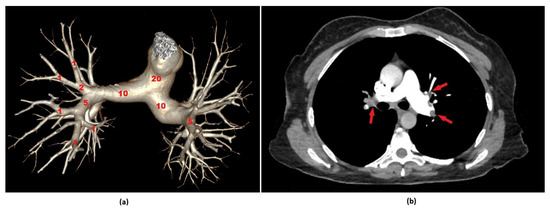

2.4. Radiological Evaluation—Calculation of the Pulmonary Artery Obstruction Index (PAOI)

- Qanadli, S.D.; El Hajjam, M.; Vieillard-Baron, A.; Joseph, T.; Mesurolle, B.; Oliva, V.L.; Barre, O.; Bruckert, F.; Dubourg, O.; Lacombe, P. New CT index to quantify arterial obstruction in pulmonary embolism: Comparison with angiographic index and echocardiography. Am. J. Roentgenol. 2001, 176, 1415–1420. [Google Scholar] [CrossRef]